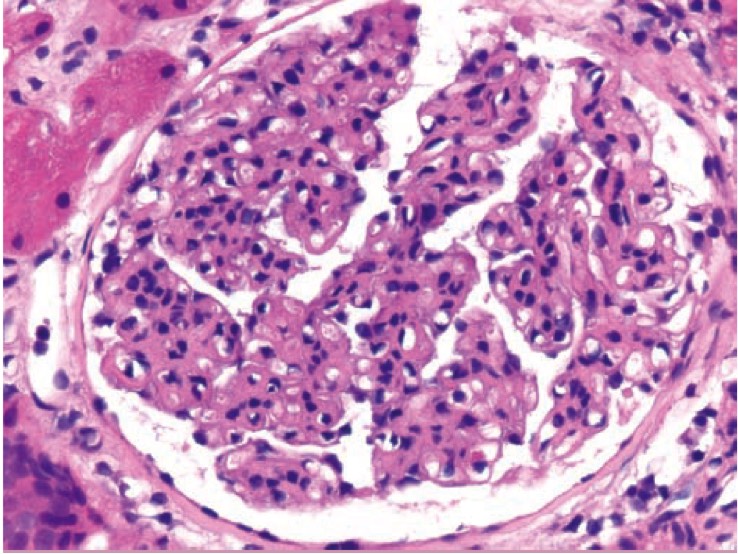

1005. На микрофотографии показан биоптат почки пациентки с активным волчаночным нефритом, обычно иммунные комплексы в нефроне откладываются